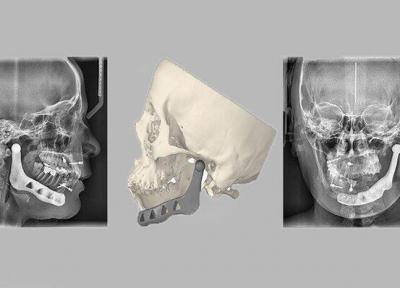

پروتز فک پایین با روش پرینت سه بعدی ساخته شد

به گزارش خبرنگاران، پروتز سفارشی مندیبل به روش پرینت سه بعدی که کار تحقیقاتی مشترک پژوهشگران دانشگاه های تهران، صنعتی شریف و علوم پزشکی تهران است، 5 مرداد ماه 98 در جراحی موفقیت آمیز در صورت یک بیمار کار گذاشته شد.